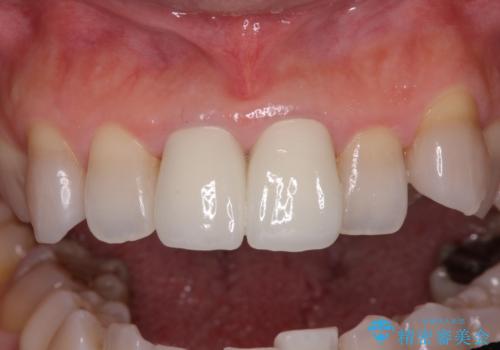

変色した前歯 オールセラミッククラウンにより審美歯科治療

- 変色した前歯2本を気にして来院された患者様です。

右側の前歯は根管治療を行い、その後2本とも歯質に近い素材の土台を植立してオールセラミッククラウンにて補綴することとしました。